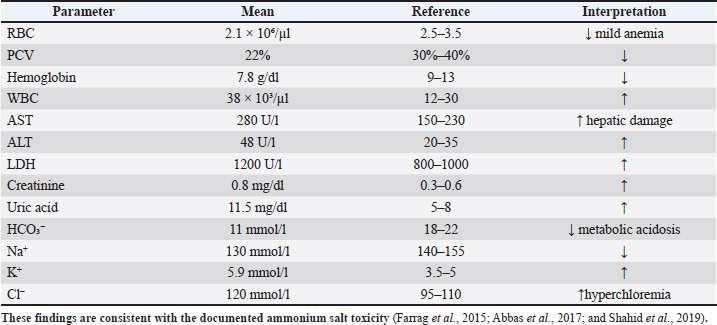

Fig. 4. Enlarged kidneys with marked congestion and swelling. Hematological and biochemical findingsTen affected birds were examined.The findings (Table 1) included anemia, leukocytosis, metabolic acidosis, hyperchloremia, elevated liver enzymes, and renal impairment—consistent with ammonium-induced toxicity (Shahid et al., 2019; Ahmad et al., 2021). Table 1. Hematological and biochemical alterations in poultry ammonium chloride toxicity.